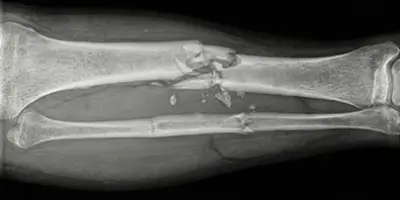

Parçalı kırık (komminüte kırık), kemiğin birden fazla parçaya ayrıldığı ciddi kırık türüdür. Nedenleri, belirtileri, teşhisi ve tedavisi hakkında bilgi.

Tibia (kaval) kemiğinde görülen nadir ve yavaş seyirli kötü huylu tümör Adamantinoma hakkında bilmeniz gerekenler ve tedavi süreci.